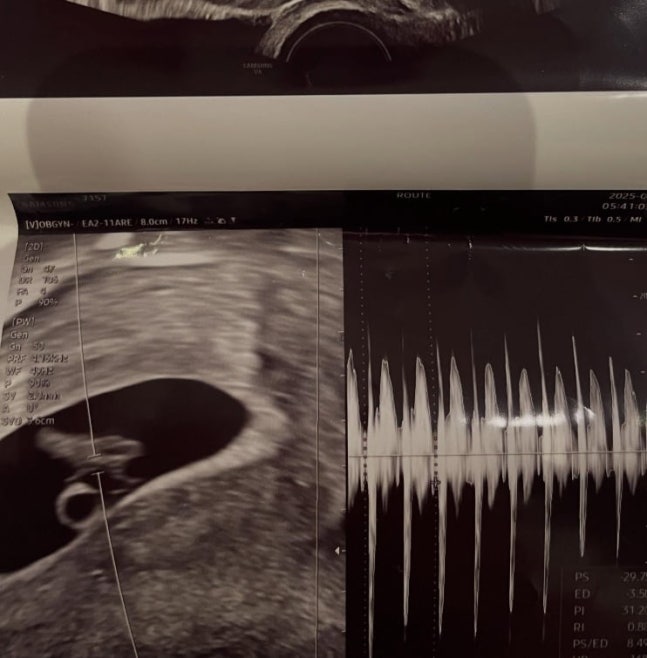

2일 서민재는 자신의 SNS에 "아빠 된 거 축하해 정래성"이라는 글과 함께 여러 사진을 게재했다.

공개된 사진 속 서민재는 일반인 남성과 다정한 스킨십을 하며 럽스타그램을 보였다. 특히 그는 아이의 초음파 사진을 공개하며 팬들의 궁금증을 자아내기도 했다.